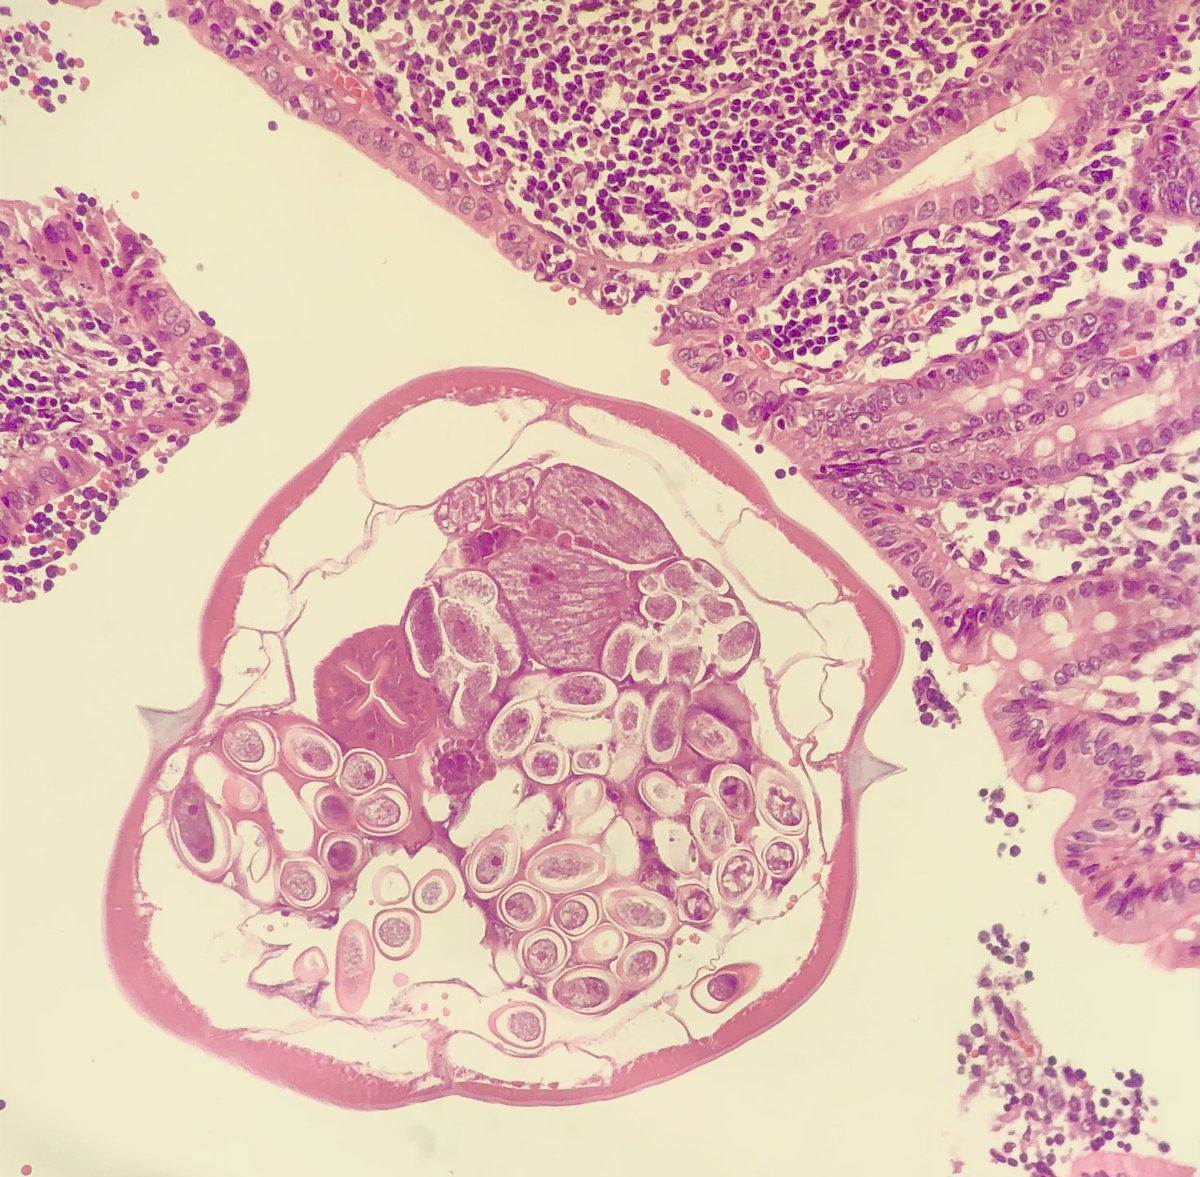

These appendix just keep choosing my routines! Male, 4 yo, โ€œappendicitisโ€. You know the drill... knock knock whoโ€™s there? ๐Ÿ‘€ #knockknock #crittersontwitter #pathbugs #appendix #pathology #pathresidents